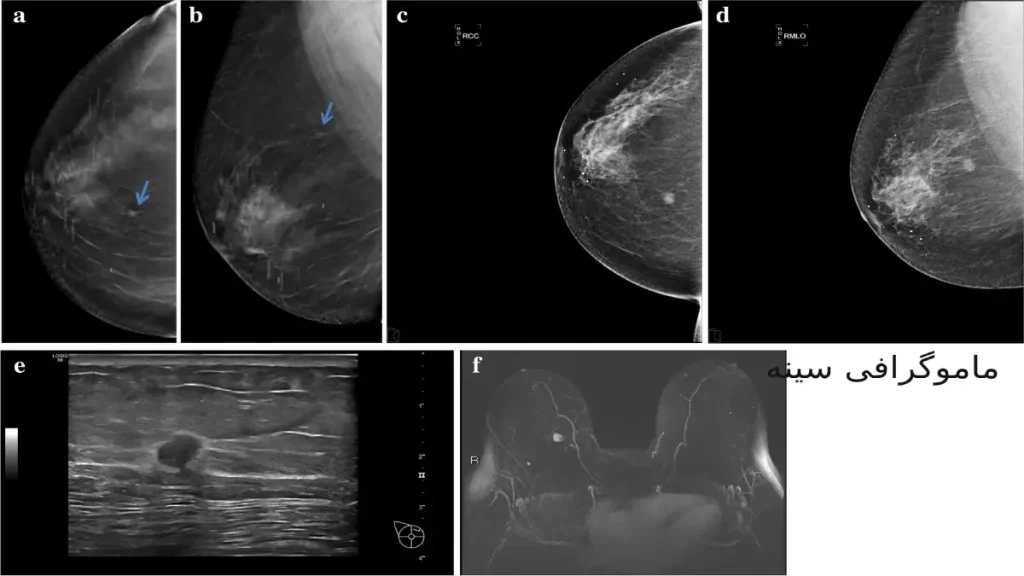

A mammogram is an X-ray image of your breasts. It can be used either for breast cancer screening or for diagnostic purposes, such as to investigate symptoms or unusual findings on another imaging test.

During a mammogram, your breasts are compressed between two firm surfaces to spread out the breast tissue.

Then an X-ray captures black-and-white images that are displayed on a computer screen and examined for signs of cancer.

ماموگرافی یک تصویر اشعه ایکس از سینه شما است. این می تواند برای غربالگری سرطان سینه یا برای اهداف تشخیصی، مانند بررسی علائم یا یافته های غیر معمول در یک آزمایش تصویربرداری دیگر استفاده شود.

در طول ماموگرافی، سینه های شما بین دو سطح سفت فشرده می شود تا بافت سینه پخش شود. سپس اشعه ایکس تصاویر سیاه و سفیدی را می گیرد که بر روی صفحه کامپیوتر نمایش داده می شود و از نظر علائم سرطان بررسی می شود.